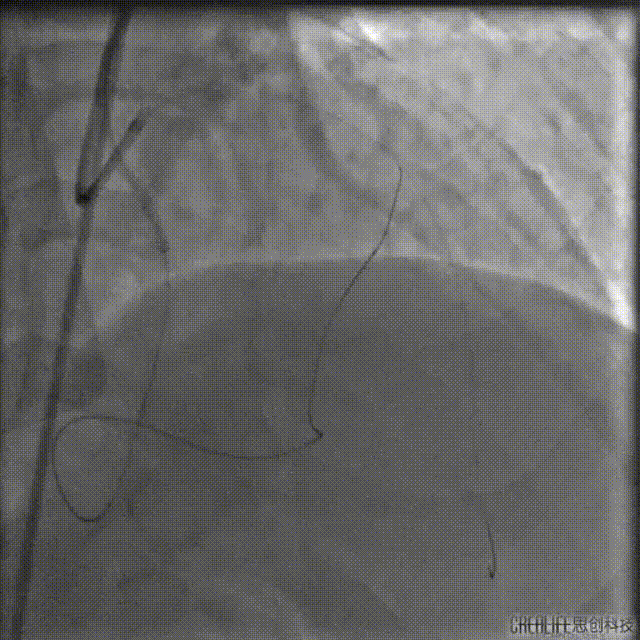

再次尝试正向开通

通过双腔微导管送入P200导丝Kissing逆向导丝,最终在肝位Kissing进入LAD远段。

送入2.0*20mm球囊对病变段进行扩张。

再次送入IVUS超声导管至LAD远段回撤,结果显示导丝全程位于真腔,近端见钙化及少量血肿。

由远及近串联植入2.5*36mm、2.75*36mm、3.5*29mm支架三枚。

支架释放后造影,中段支架膨胀欠佳。